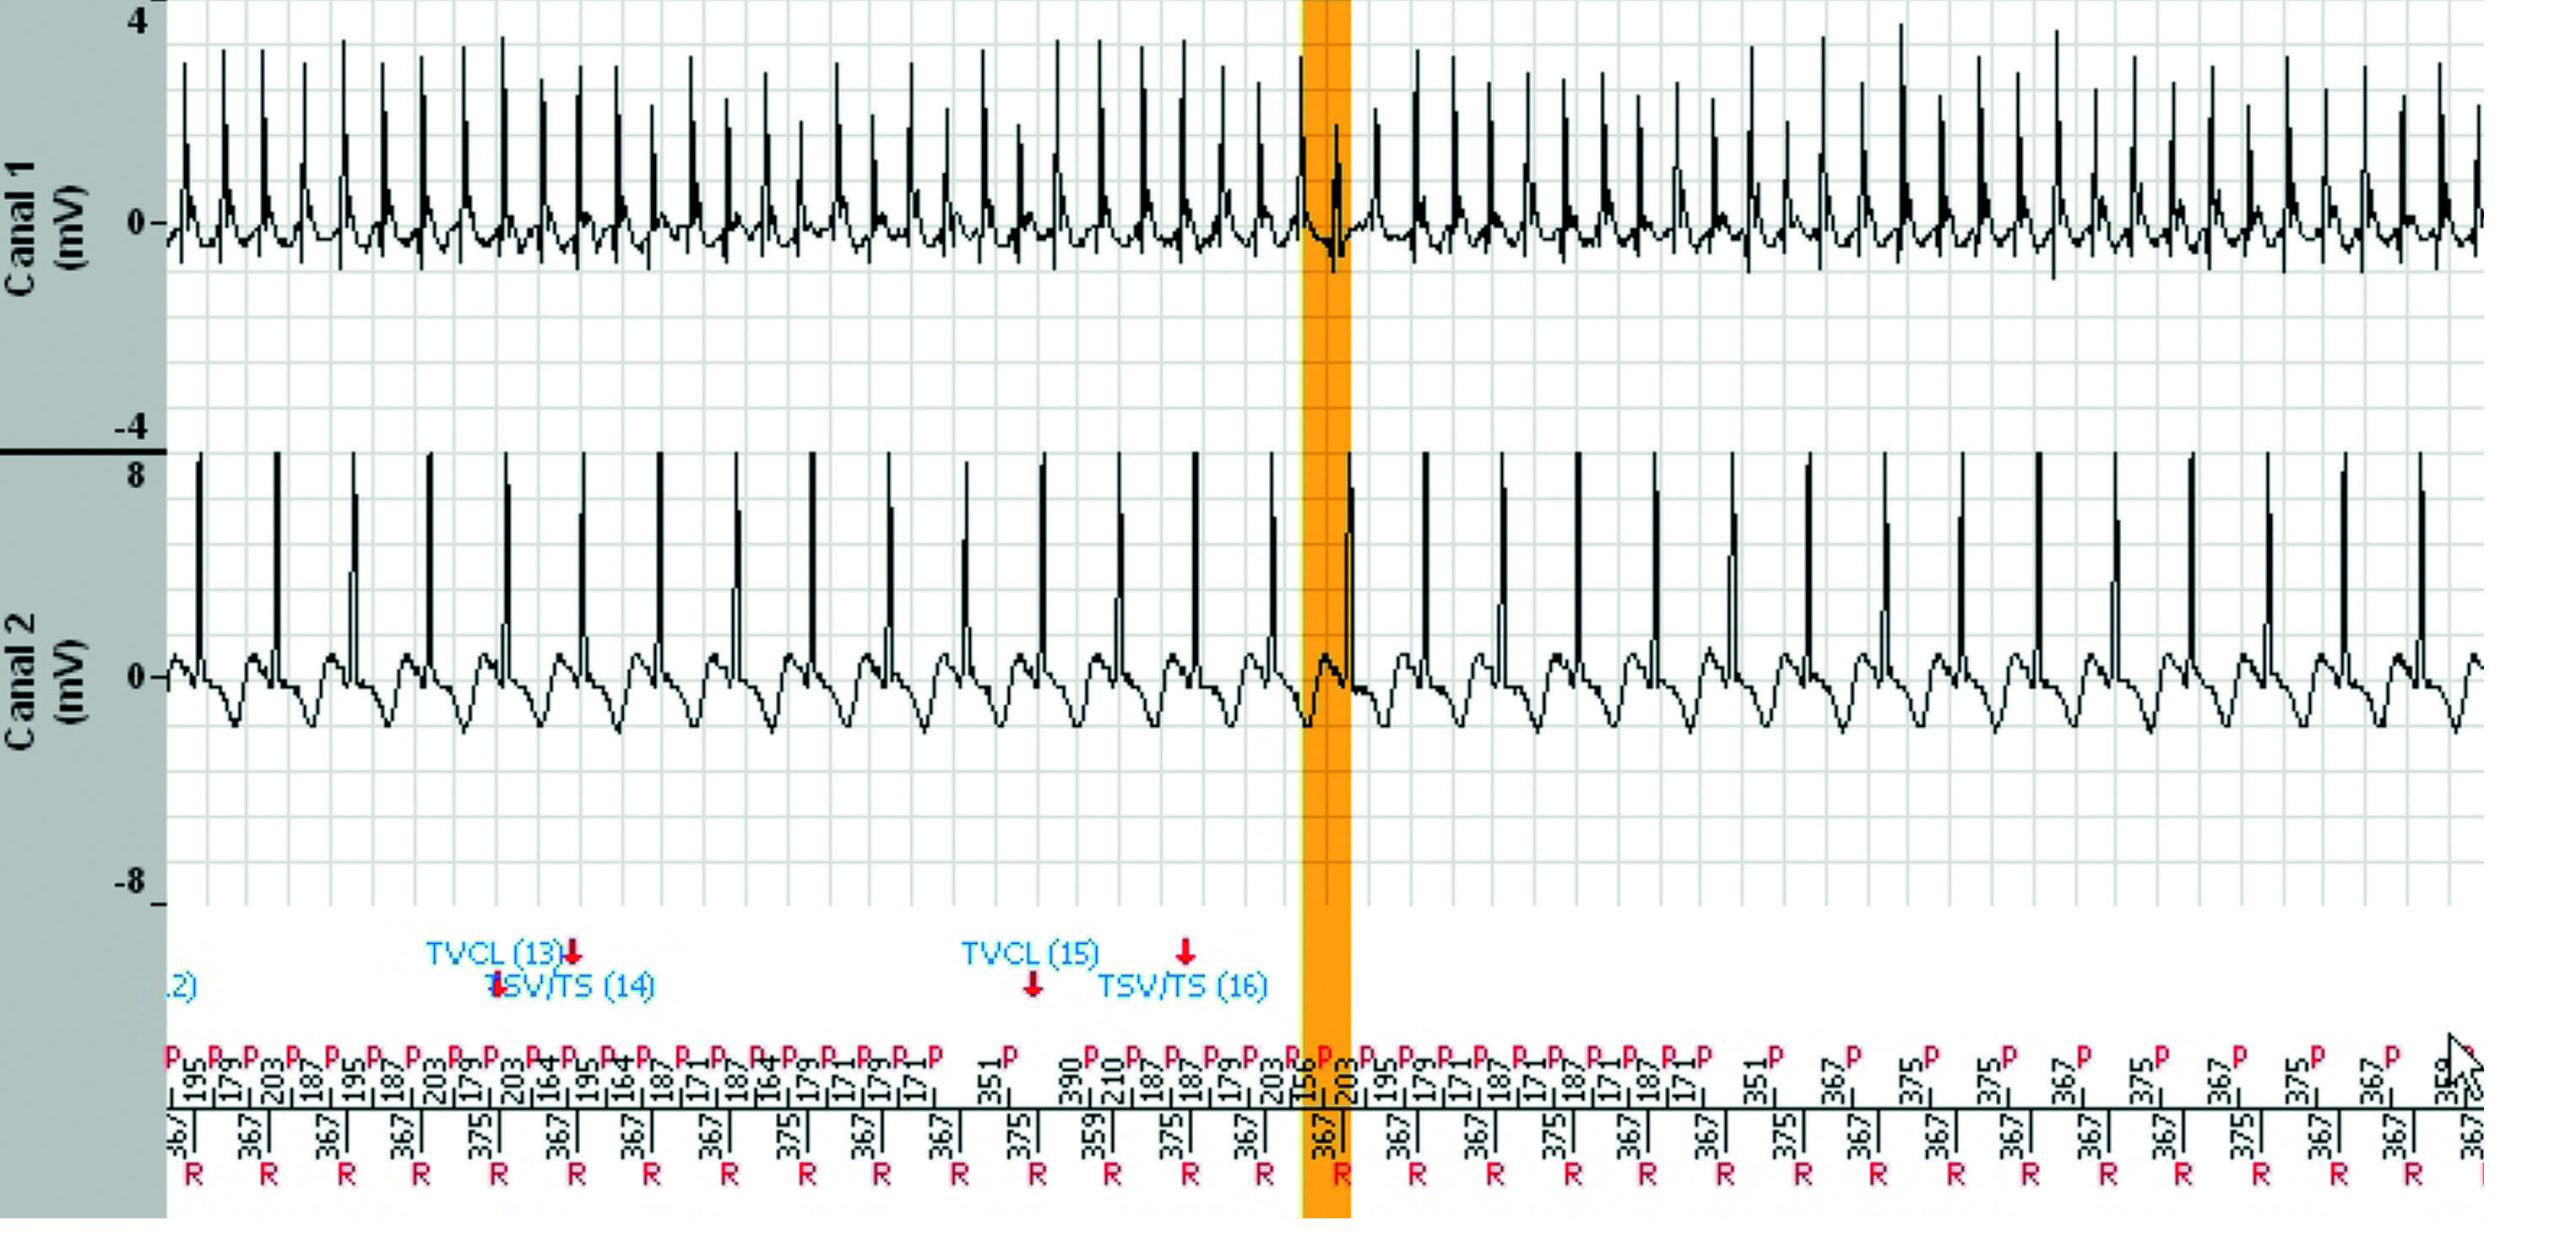

L'épisode a duré 7 minutes et 38 secondes et le tachogramme ci-dessous ne montre que les 3dernières minutes. Pendant les 4 minutes et 30 secondes précédentes, la fréquence ventriculaireest parfaitement stable dans la zone de TV lente.

Un diagnostic correct ne peut résulter que d'une analyse méticuleuse de toutes les informations stockées par l'appareil.

Les statistiques, les courbes d'évolution des paramètres et tous les EGM doivent être analysés.

La fonction “ Analyse “ des EGM est un outil précieux pour comprendre le fonctionnement de l'appareil et pour déterminer la reprogrammation nécessaire.